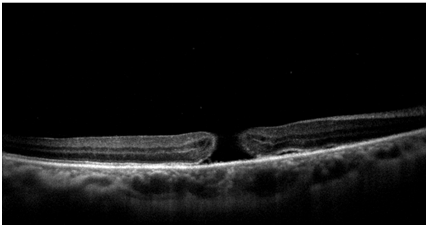

Optical coherence tomography (OCT) was performed to confirm the macular hole seen at the fundus examination (Figure 1). The patient was surgically treated with posterior pars plana vitrectomy and peeling of the internal limiting membrane with the aid of the Brilliant Blue dye, followed by tamponade with SF6 gas. It progressed satisfactorily after surgery, with improvement of visual acuity and absence of macular hole at funduscopy. At OCT, it presented macula compatible with post-surgical reorganization, with no evidence of a macular hole. About 1year after the procedure, the patient presented visual acuity of 20/80 with the best correction in OD and no evidence of macular hole to the OCT (Figure 2).

Figure 2 OCT performed in the late postoperative period.